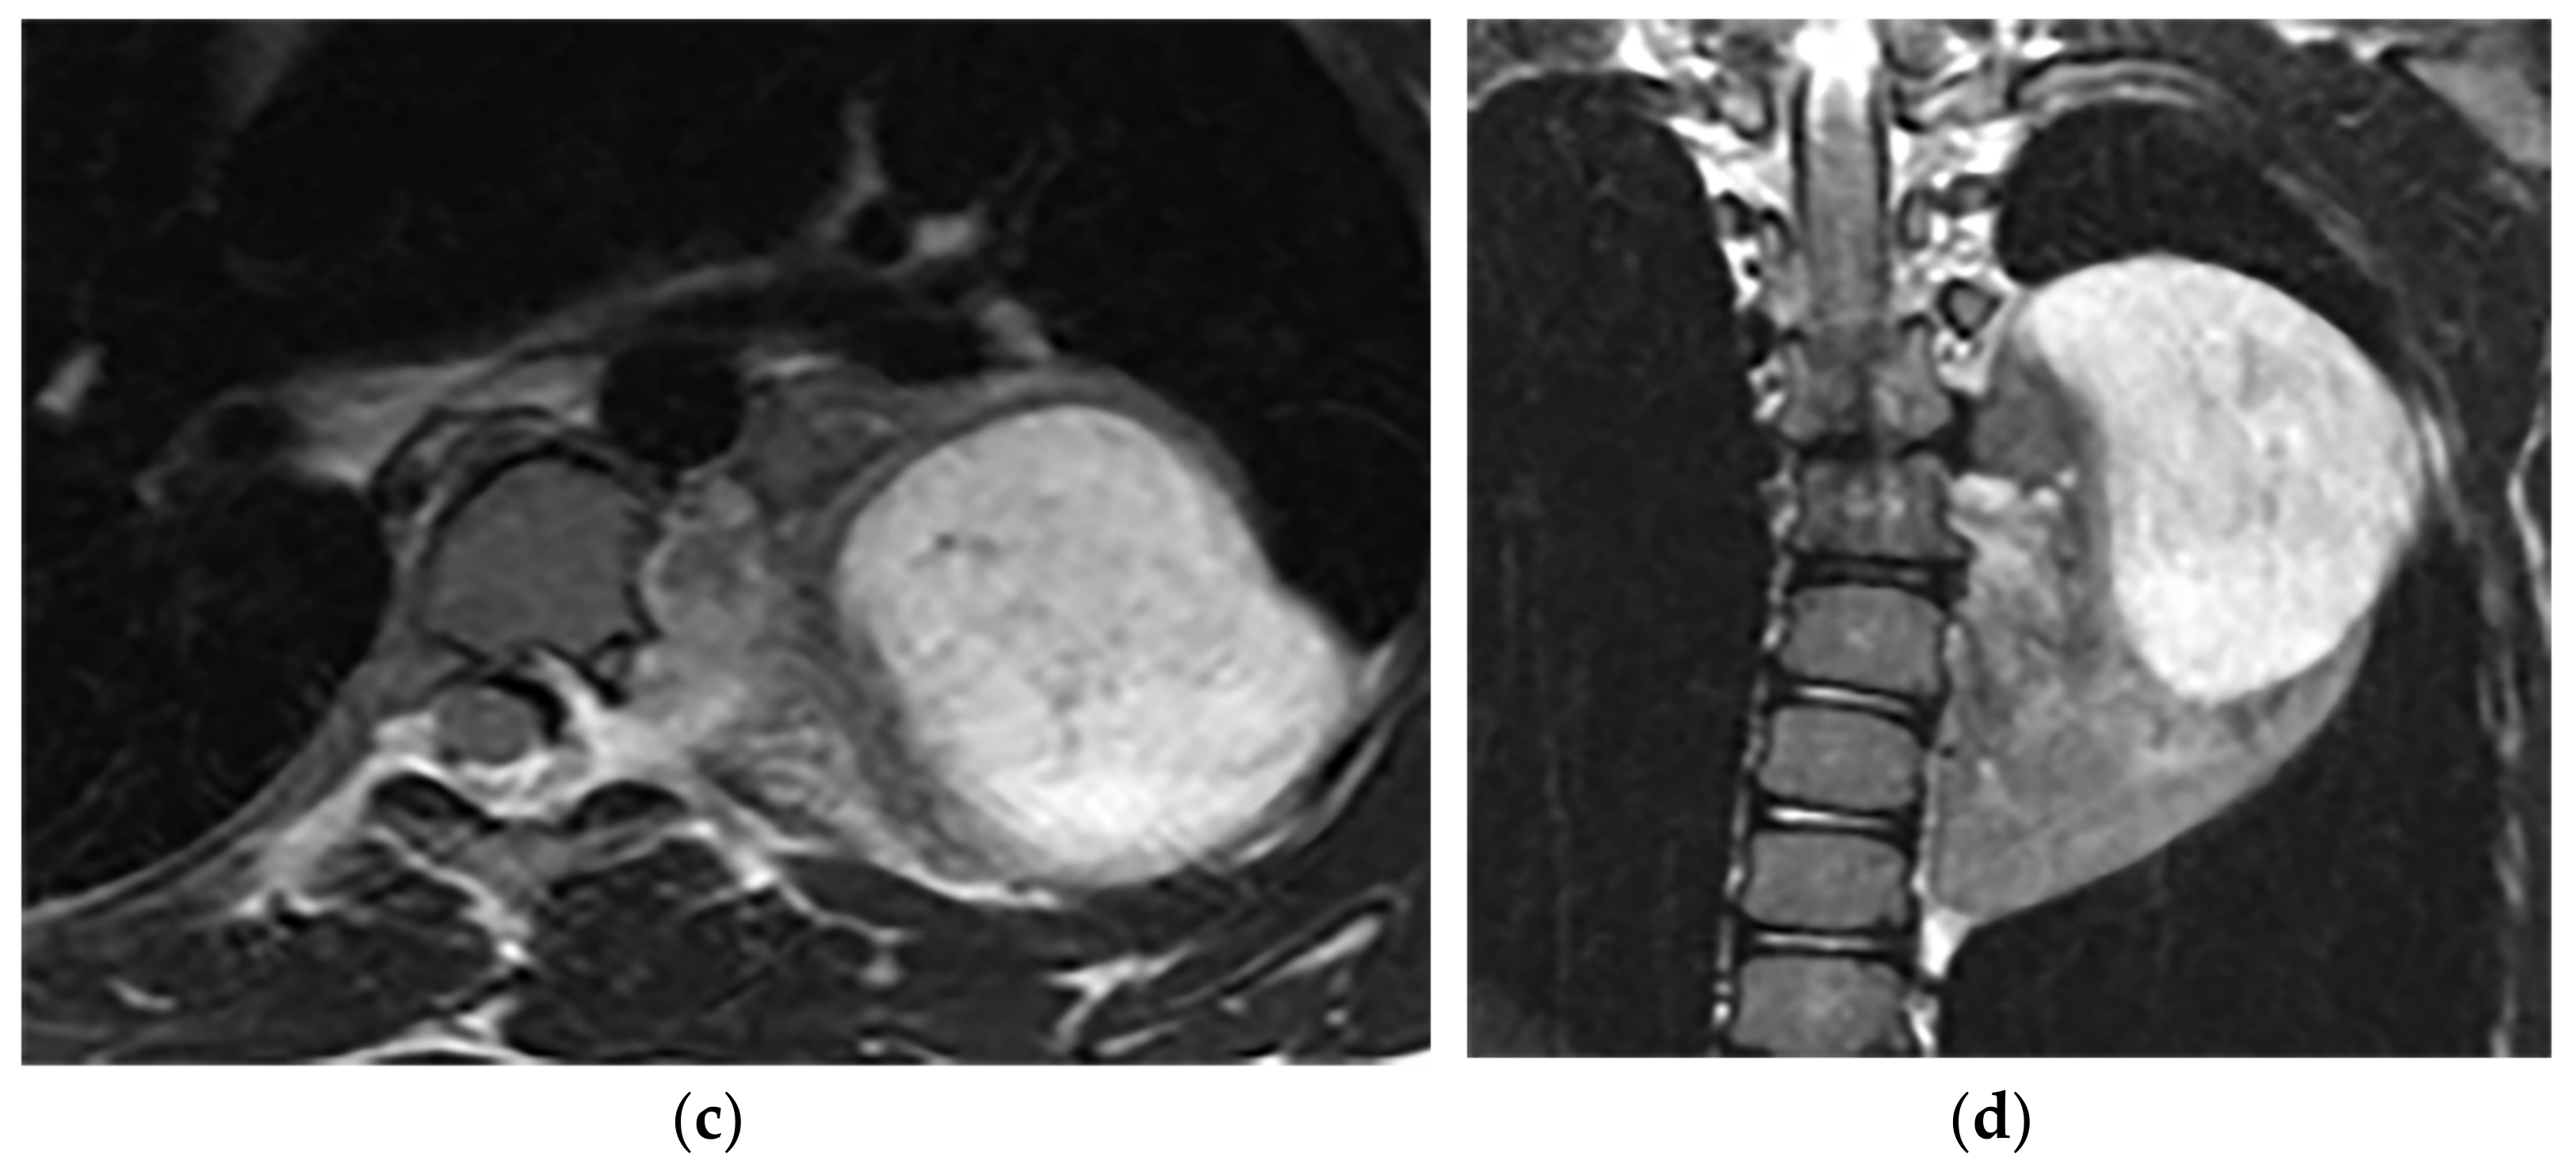

| Ganglioneuroma [7,16,43] | Homogenous or heterogeneous attenuation with internal calcification in 25% of cases. | T1W, T2W: intermediate signal with the curvilinear or nodular low signal band making the whorled appearance |